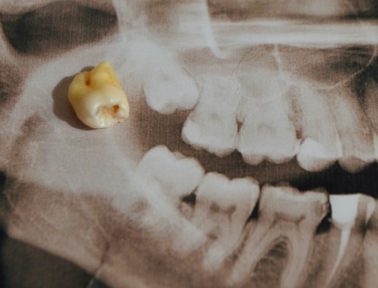

Oct 03

Tooth decay, also known as dental caries or cavities, is a very common oral health issue that can have far-reaching consequences, if left untreated. It can lead to other oral health concerns and is linked to general health conditions.